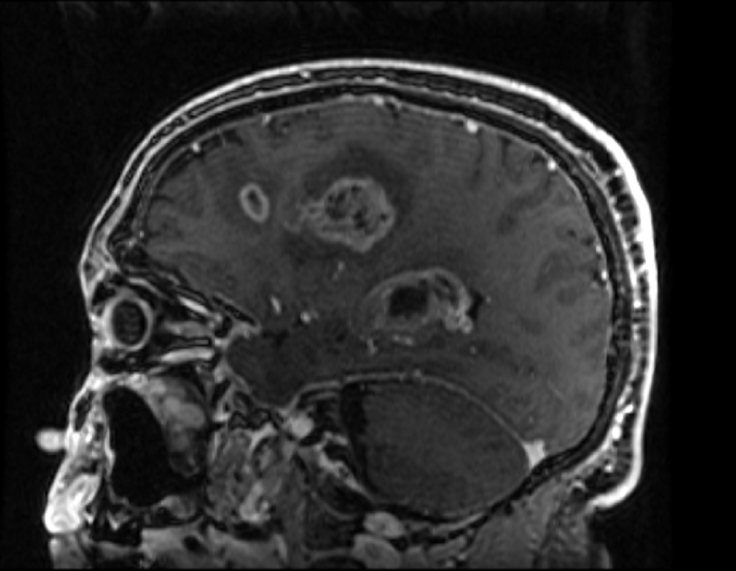

This middle aged patient had a heterogeneous lesion with multiple irregular rings of enhancement following contrast administration. Biopsy revealed glioblastoma with microvascular proliferation and necrosis, both of which contain leaky blood vessels that contribute to contrast enhancement on imaging.